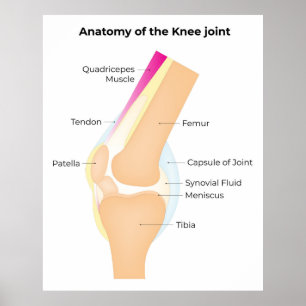

Poster Anatomia do joelho

Preço175,00 €